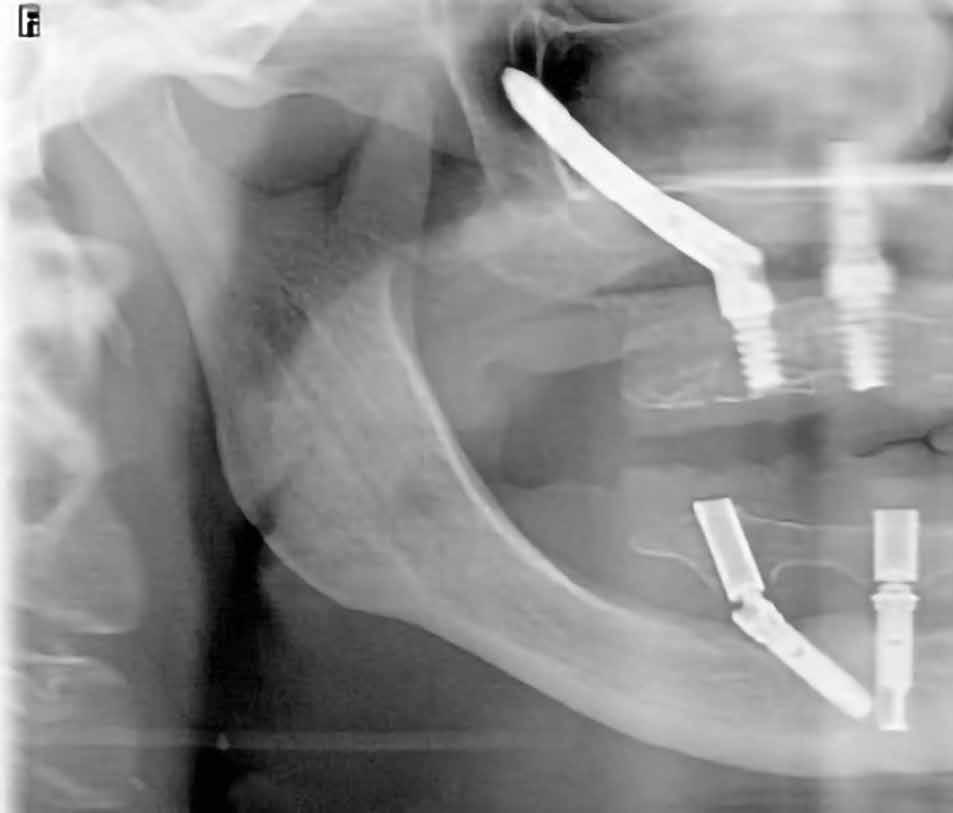

heléssel vagy anélkül). Az első páciensnél gyökérreszorpció miatt szükségessé vált a jobb felső premolárisok és az első moláris eltávolítása (1. a–b ábrák). A második páciensnél a bal felső második premoláris frakturát szenvedett (1. c–d ábrák) Az átfogó tervezést és diagnosztikát CBCT-felvétel segítségével végeztük (2. a–c ábrák), a posztoperatív kontroll és az utánkövetés időszakában pedig periapikális röntgenfelvételeket készítettünk. A jelen tanulmányban résztvevő valamennyi páciens nemdohányzó volt, jó, vagy gyógyszeresen jól karbantartott általános egészségi állapotnak örvendett. A hatékony plakk-kontroll ellenére műtét előtt mindkét páciensnél végeztünk supragingivális depurálást és gyökérsimítást.

2. a–c ábrák: Kiindulási CBCT-felvételek.

A 64 éves kaukázusi nőpáciens 2004 óta áll gondozásunk alatt, az alsó fogíven sikeres All-on-4 kezelésen van túl (1. ábra). Felső állcsontja több mint harminc éve fogatlan, de erősen motivált a sebészi rehabilitációra. A páciens elsődleges célja egy fix fogpótlás volt, amely helyreállítja a rágófunkciót és az esztétikus megjelenést (2. ábra).

21. ábra: A hangár technika okkluzális nézetből. – 22. ábra: A posztoperatív panorámaröntgen, amelyen látszik a jobb felső kvadráns augmentált területe. A hangár technika lehetővé tette az augmentáció és az implantáció egyidejű elvégzését. 23. ábra: A feltárás és a gyógyulási fej behelyezése. – 24. ábra: A feltárást követően készült panorámafelvétel, amelyen a gyógyulási fej látható.